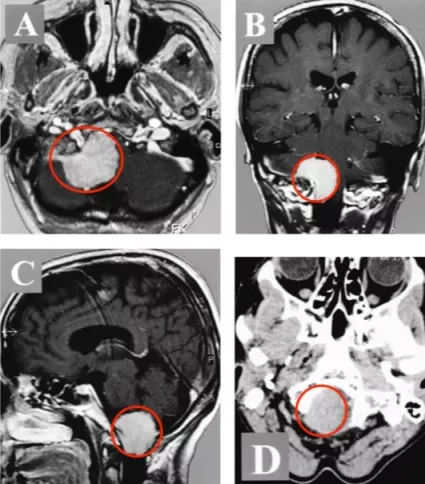

一年後的一個晚上,當Belle出現走路乏力、雙腳抬不起來時,一切都變了。她差點摔倒在地,但幸運的是,家人在她摔倒前抓住了她。他們開始意識到這病沒那麼簡單,不查不知道,一查嚇一跳,最終發現原來引起上述症狀的罪魁禍首不是什麼頸椎病,而是在枕骨大孔區區長了一個腫瘤-腦膜瘤(圖1)。雖然腦膜瘤90%以上都是良性腫瘤,但其生長的部位實在是太要命了,腫瘤位於下腦幹枕骨大孔區,並嚴重壓迫和推擠腦幹延髓。加上腫瘤發現的太晚了,體積巨大,導致下腦幹在枕骨大孔處被最大限度地壓縮,腫瘤佔據了90%以上的可用空間。

圖1:術前MR顯示枕骨大孔區巨大腦膜瘤,壓迫腦幹、頸髓。

術後CT和MR,顯示腫瘤及其被腫瘤侵犯的骨質都切除,腫瘤全切,Simpson一級切除。